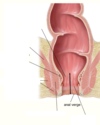

What are the two sections of the perineum (anterior and posterior)?

Urogenital triangle and anal triangle.

The smooth area of the bladder is called the ________. It has _ openings they are….

Trigone: 3 opennings, one for the internal urethral orifice, 2 for the ureteric orifaces.